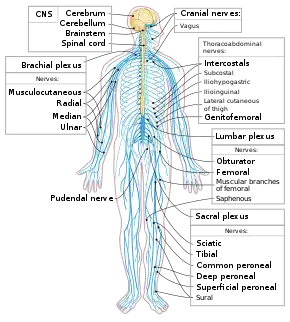

Neurological disorders can be categorized according to the primary location affected, the primary type of dysfunction involved, or the primary type of cause. The broadest division is between central nervous system disorders and peripheral nervous system disorders. The Merck Manual lists brain, spinal cord and nerve disorders in the following overlapping categories:[10]

| Nervous system | |

Human nervous system | |

- Spinal cord disorders (see spinal pathology, injury, inflammation)

- Peripheral neuropathy and other Peripheral nervous system disorders

- Cranial nerve disorder such as Trigeminal neuralgia

- Autonomic nervous system disorders such as dysautonomia, multiple system atrophy